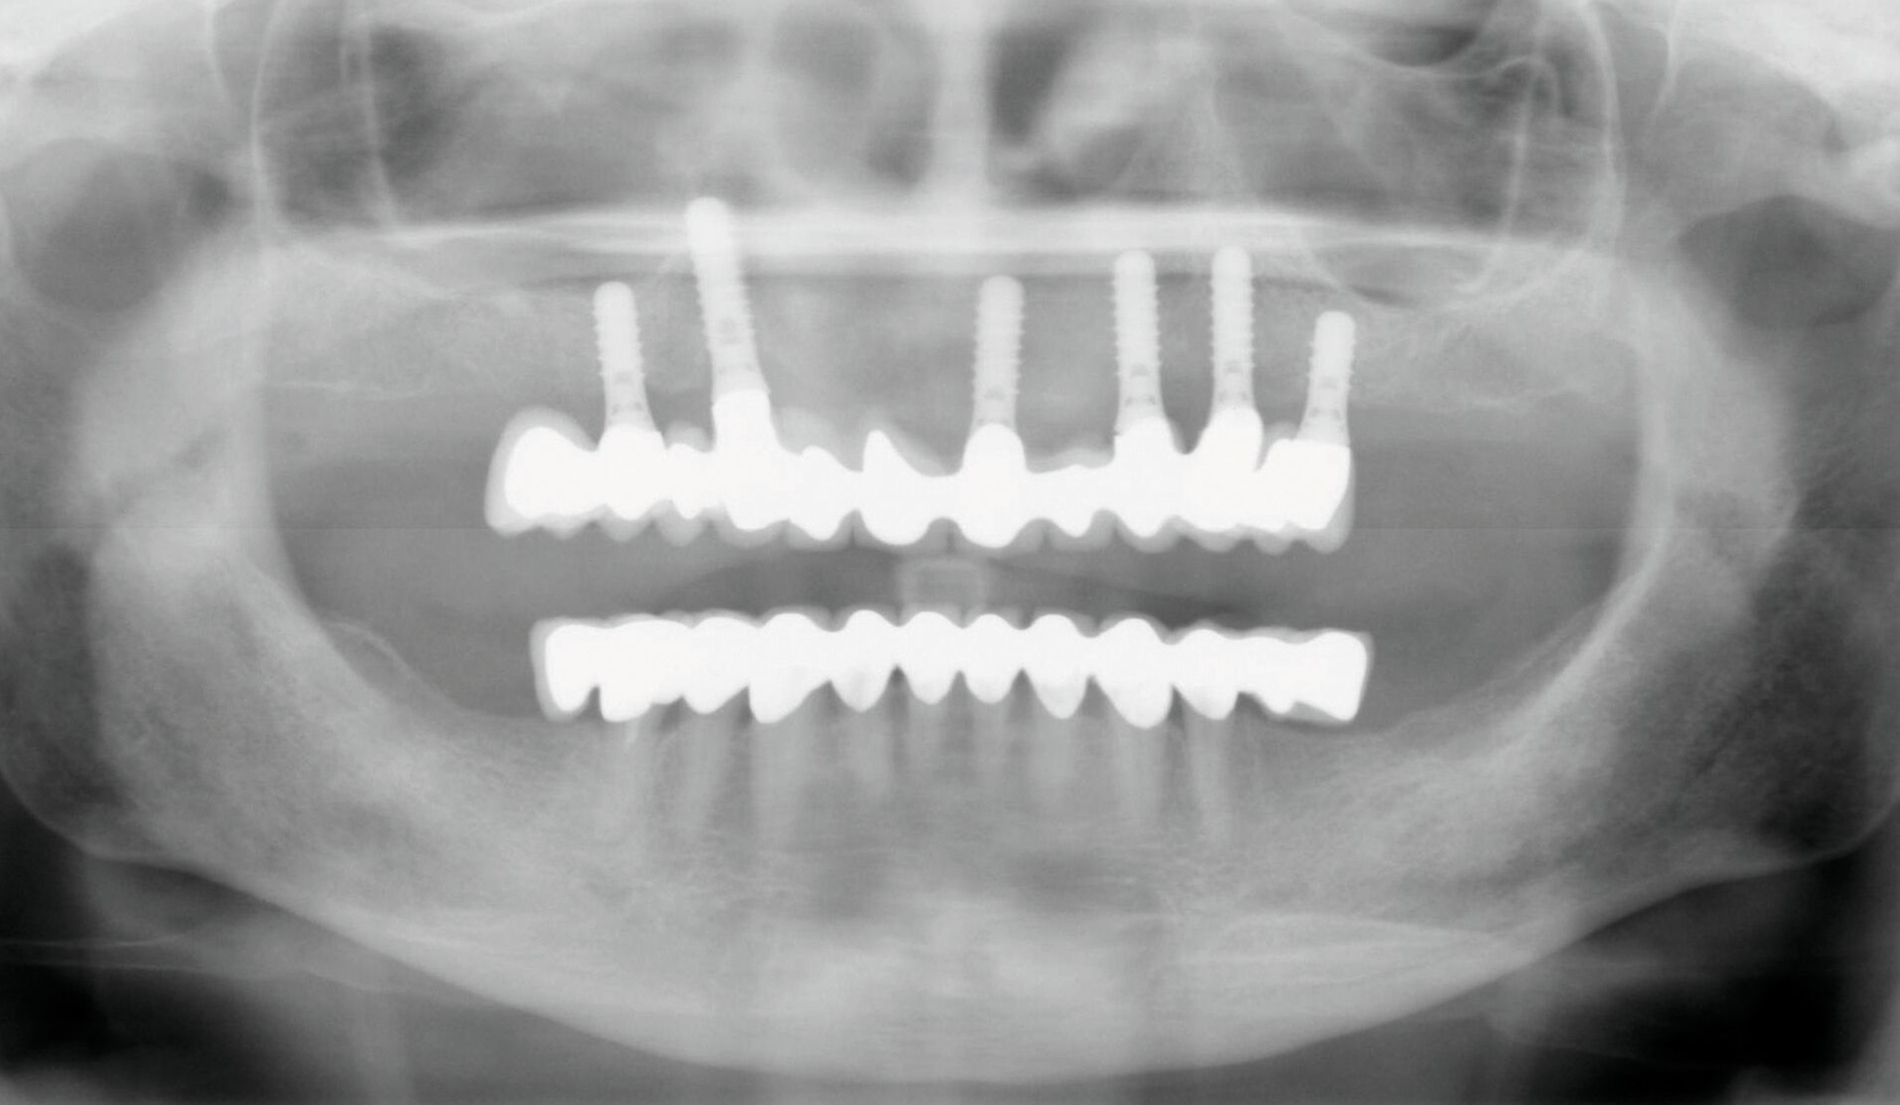

In einer von Kiel initiierten, DFG-geförderten, multizentrischen Studie mit 158 Ein-Implantat-Prothesen war die Implantat-Verlustrate nach fünf Jahren bei Sofortbelastung des Implantats höher als bei Spätbelastung (15,3 Prozent versus 3,8 Prozent) [Kern et al., 2018]. Die neun Implantatverluste in der Sofortbelastungsgruppe traten in den ersten drei Monaten nach Insertion auf. In der Spätbelastungsgruppe musste ein Implantat bei der Freilegung und ein weiteres nach fünf Jahren entfernt werden (Abbildung 3). Die postoperativen Beschwerden waren bei Sofortbelastung höher als nach Spätbelastung [Mundt et al., 2017]. Nach der Prothesenstabilisierung war eine deutliche Verbesserung der Kaueffizienz ohne Unterschiede zwischen den Belastungsprotokollen zu beobachten, die den gesamten Fünf-Jahres-Beobachtungszeitraum anhielt [Passia et al., 2022]. Die Patientenzufriedenheit [Passia et al., 2017] und die mundgesundheitsbezogene Lebensqualität [Schwindling et al., 2018] wurden ebenfalls spürbar verbessert.

Der Nachsorgeaufwand scheint jedoch nicht unerheblich zu sein. Von den über fünf Jahre nachverfolgten 102 Prothesen mussten 37 wegen Prothesenbasisfrakturen repariert werden, darunter elf mehrmals. Weiterhin wurde 123 Matrizeninserts und 14 Kugelköpfe im Studienverlauf ausgetauscht. Mögliche Komplikationen bei Ein-Implantat-Prothesen werden in einer Literaturübersicht mit einer berechneten jährliche Frakturrate von 10,8 pro 100 Kugelanker-Prothesen und 16,8 Nachsorgemaßnahmen pro 100 Locator-Prothesen bestätigt [Padmanabhan et al., 2020]. Die nachträgliche Einarbeitung einer Metallbasis verhindert Basisfrakturen [Pinheiro et al., 2021]. Insgesamt scheint die Ein-Implantat-Prothese im Unterkiefer eine einfache, minimalinvasive und kostengünstige Alternative mit hohen Implantatüberlebensraten bei Spätbelastung für ältere Patienten zu sein, die einem Vergleich mit Zwei-Implantat-Prothesen standhält. Bei der Wahl dieser Therapievariante für den Unterkiefer bei kompletter Zahnlosigkeit sollte der Nachsorgeaufwand berücksichtigt werden. Eine Sofortbelastung des mittig stehenden Implantats bleibt Ausnahmefällen vorbehalten.